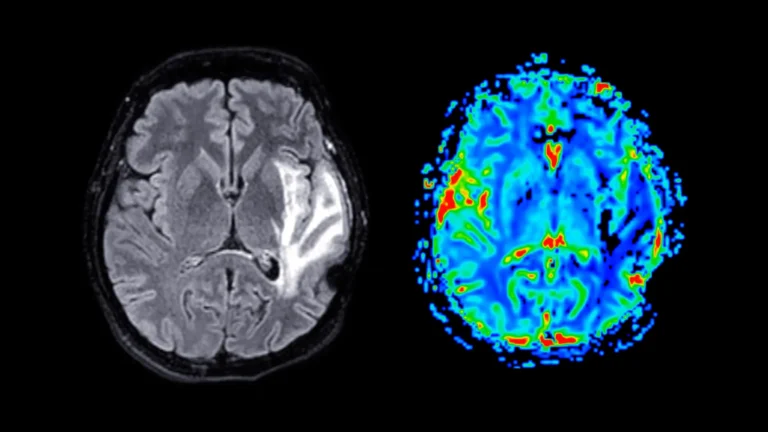

An extensive international research initiative has uncovered significant variations in how individuals experiencing long COVID report neurological...